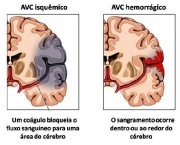

Ela é comum em casos de acidentes vascular cerebral, ou quando há outros danos ao sistema neurológico que fazem com que a pessoa que sofre de tal problema não consiga mais reconhecer a escrita, ou então executar a fala como podia antes de tais acidentes.